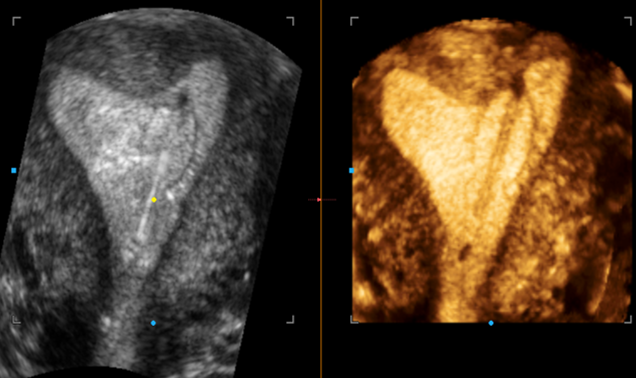

Современные экспертные УЗИ сканеры дают возможность проводить исследования всех органов в 3D. Это позволяет, используя полученный массив данных, получать диагностические сечения в любой плоскости, недоступной для обычного 2D УЗИ. Наиболее интересной является фронтальная. Например, визуализация полости матки. Диагностическая возможность выявления пороков развития превосходит все другие методы (рентгеновские и МРТ). Метод также позволяет уточнить положение ВМК (спирали) в полости матки, расположение миоматозных узлов, расположение плодного яйца на малых сроках, полипов. Сегодня современное экспертное ультразвуковое исследование невозможно без использования 3D УЗИ.